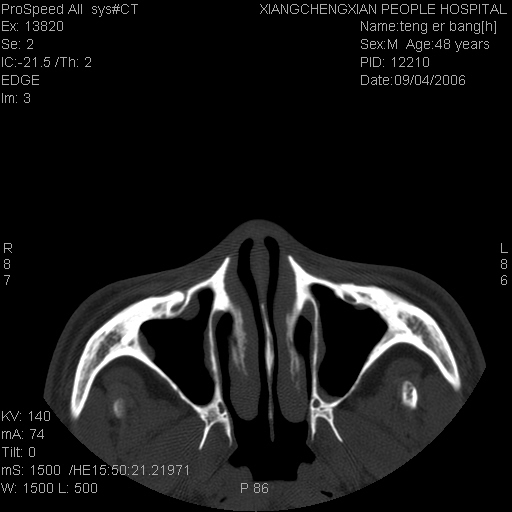

ct:平扫+冠扫:双侧鼻骨对比,冠扫s6#示右侧鼻骨尖部可见线状低密度影,边缘光滑,并见硬化.软组织未见肿胀.

诊断意见:鼻额缝(鼻骨与上颌骨额突缝),但个别同志认为是骨折.因此请同行们会诊.多谢了!

正常的,双侧对称.边缘光整,且逢等宽.